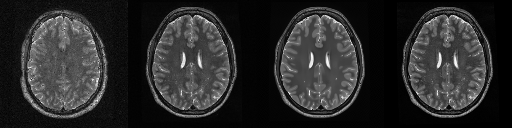

HCP T2w dataset

We utilize images from the publicly available Human Connectome Project (HCP) [51] T2-weighted (T2w) images dataset for the task of compressed sensing, which contains brain images from 47 patients. The HCP dataset includes cross-sectional images of the brain taken at different levels and angles.

Compressed sensing

We train a flow-based model from scratch on 10,000 randomly sampled images, utilizing the ncsnpp architecture [9] with minor adaptations for grayscale images. We employ compression rates , meaning . The measurement operator is given by a subsampled Fourier matrix, whose sign patterns are randomly selected. We evaluate our reconstruction algorithm’s performance on 200 randomly sampled test images.

We present the quantitative and qualitative results of compressed sensing in Tab. 1 and Fig. 4, respectively. As shown in Tab. 1, our method consistently achieves the best performance across varying compression rates . In Fig. 4, our method produces reconstructions that are more faithful to the original images, with fewer artifacts, leading to higher accuracy and clearer details.